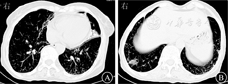

患者女,68岁,农民,2月前因"反复发热、咳嗽咳痰伴咽痛、乏力"入住当地医院。患者2017年9月起无明显诱因下出现间歇性发热,低热为主,具体体温不详,以下午及傍晚明显,伴咳嗽,咳黄色(后转白色)黏痰,伴全身乏力、咽痛、颈前区疼痛、恶心、心慌胸闷,无呕吐,无鼻塞流涕,无腹痛、腹胀、腹泻,无胸痛烧心,无畏寒怕热,无盗汗消瘦,无四肢麻木等。诊断为弥漫性毒性甲状腺肿(Graves病),予泼尼松、美托洛尔等药物治疗2周后症状曾好转。后颈前区疼痛及发热乏力咳嗽等症状加剧,查肺部CT提示两肺散在多发结节,支气管炎,右肺中叶及左肺上叶下舌段支气管扩张,伴炎症机化。实验室检查:红细胞沉降率31 mm/1 h,C反应蛋白1.5 mg/L。诊断为:①Graves病;②肺部感染原因待查。11月6日转入浙江大学医学院附属第一医院进一步治疗。体格检查:体温37.7℃,脉搏110次/min,呼吸20次/ min,血压111/64 mmHg(1 mmHg=0.133 kPa)。患者神志清,精神可,双肺呼吸音粗,未闻及明显干湿啰音,心律尚齐,心率快,未闻及病理性杂音,腹软,无压痛、反跳痛,肝、脾肋下未及,肠鸣音6次/min,移动性浊音阴性,双下肢轻度凹陷性水肿,神经系统检查阴性。实验室检查:白细胞计数5.9×109/L,中性粒细胞比例0. 636,Hb 97 g/L,血小板计数159×109/L;C反应蛋白9.30 mg/L;降钙素原0.02 μg/L;肝肾功能、肿瘤标志物等正常。2017年11月10日肺部CT平扫提示:两肺多发感染性病变,两肺多发结节(图1)。入院后每天午后及傍晚有低热,体温波动于37.3~38.8 ℃,先后予左氧氟沙星、莫西沙星、头孢他啶等经验性抗感染治疗,体温仍反复波动,抗感染效果较差,怀疑肺结核可能,查结核菌素试验及结核感染T淋巴细胞斑点试验阴性;支气管肺泡灌洗液(bronchoalveolar lavage fluid,BALF)及毛刷涂片找抗酸杆菌均为阴性。2017年11月30日肺穿刺活组织检查提示:右下肺肉芽肿性炎伴坏死,抗酸阴性,痰培养抗酸杆菌2次均阴性。2017年11月28日全院多学科综合协作(multi-disciplinary team,MDT)讨论认为:肺部感染性病变首先考虑,病原体尚不明确,需考虑非结核分枝杆菌感染。继续送痰培养,后连续3次均有非结核分枝杆菌生长,菌种鉴定为鸟-胞内分枝杆菌复合群(Mycobacterium avium Complex,MAC),予利福平0.45 g+乙胺丁醇0.75 g+阿奇霉素0.5 g+莫西沙星0.4 g,1次/d联合抗感染治疗2周后,体温正常,症状基本消失,复查C反应蛋白、血常规、红细胞沉降率等基本正常,2018年2月7日肺部CT提示:病灶较前稍有吸收(图2)。出院后继续口服上述药物治疗,现已随访4个月余,病情稳定,仍继续随访中。